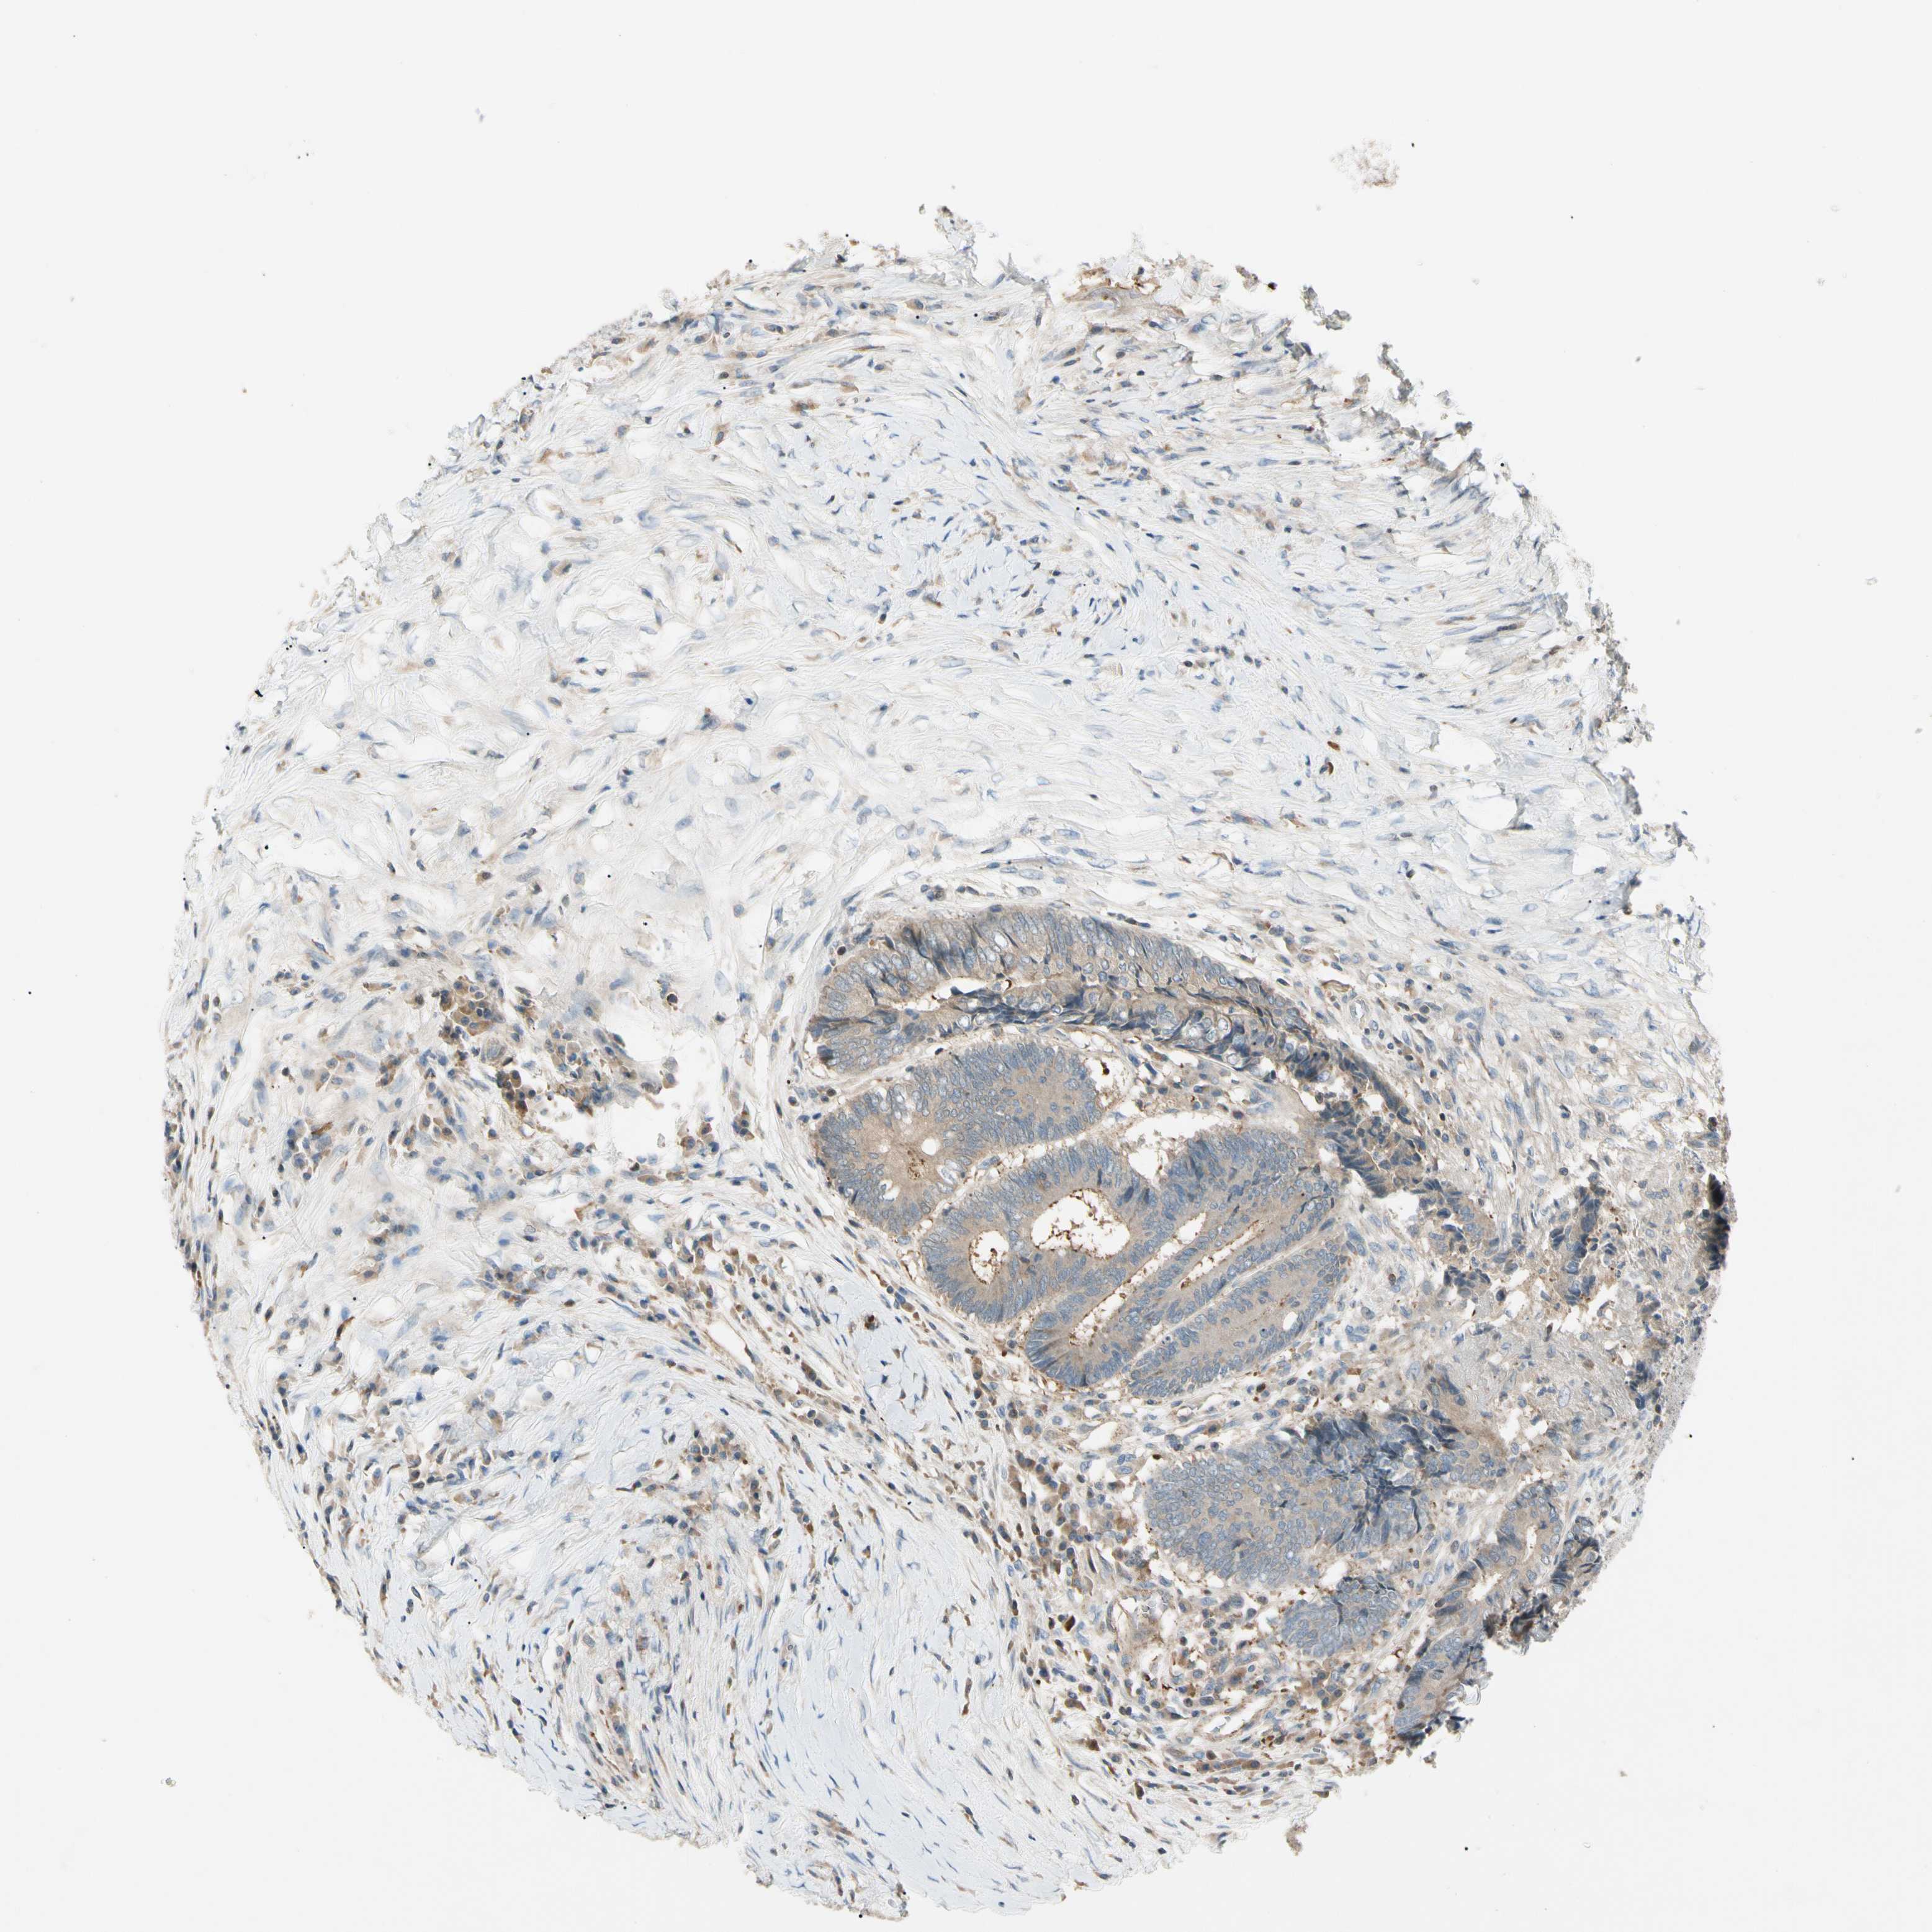

CANCER COLORECTAL CANCER Show tissue menu

Colorectal cancer

Colon adenocarcinoma